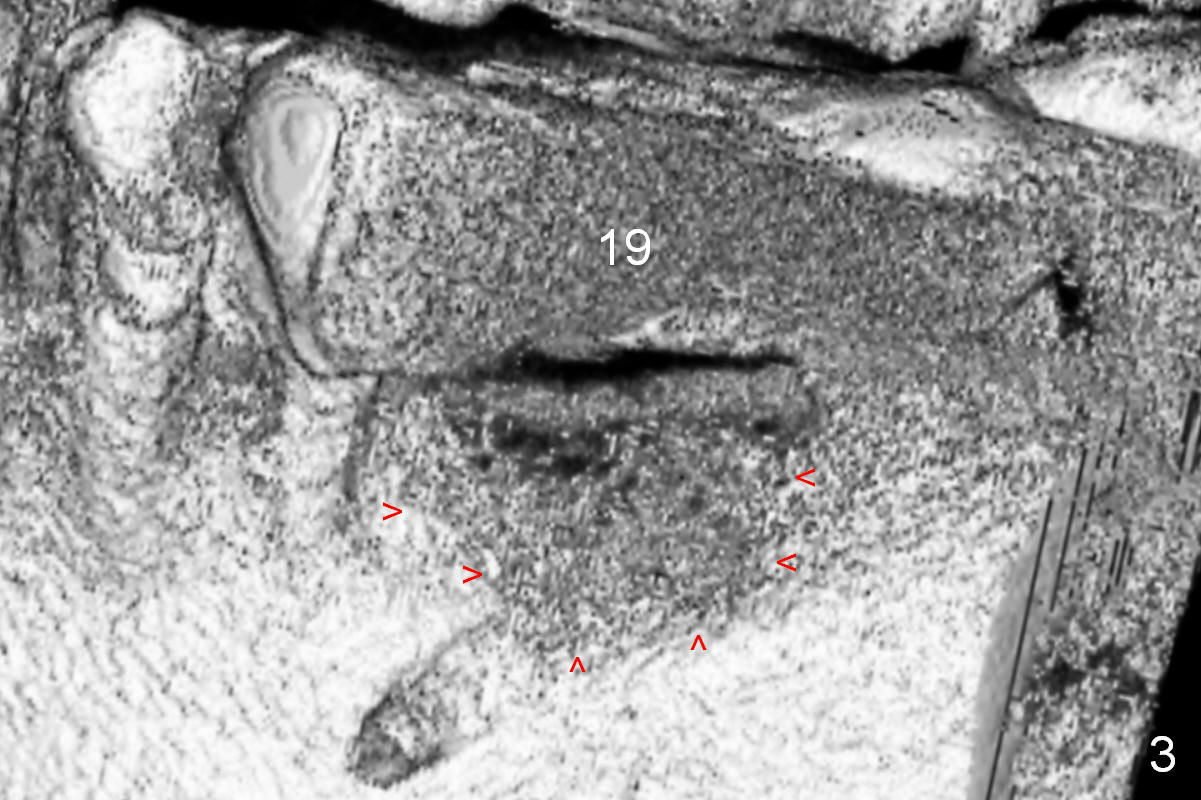

A 68-year-old lady has had a lower right bridge for 10 years (Fig.1,2 (CBCT section), Fig.3 (3 D image)). There is caries underneath #20 retainer (mesiolingual) with symptom. The retainer and the pontic at #19 will be removed. The tooth #20 may need root canal therapy. An implant will be placed at #19, but the crest is narrow (Fig.2 coronal section).

Bone density at the crest appears to be low (Fig.3 arrowheads). After pontic removal (Fig.4 black area) and incision, use #15 scalpel, bone scalpels and bone blades to start bone expansion (red line). Bone expansion continues with D osteotomes (Fig.5 red area) which mainly moves the buccal plate (B) buccally. The 3rd step of bone expansion is to use RT (round tapered) osteotomes or bone expanders (Fig.6 white circle); the buccal plate keeps being expanded more the lingual one (L). When an implant is placed, the lateral spaces created by expansion will be filled with bone graft. If the depth of osteotomy is not enough, use drills to reach the desired one.